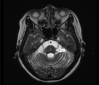

We reported a case of a 48-year-old female patient admitted to the hospital due to balance disorder which progressed rapidly within 1 week. Cerebral magnetic resonance imaging showed significant atrophy and hyperintensities at the middle cerebellar peduncles and the "hot cross bun" sign of the pons. The final diagnosis was probable multiple system atrophy, cerebellar subtype. The clinical and imaging findings will be discussed as well as a brief literature review.